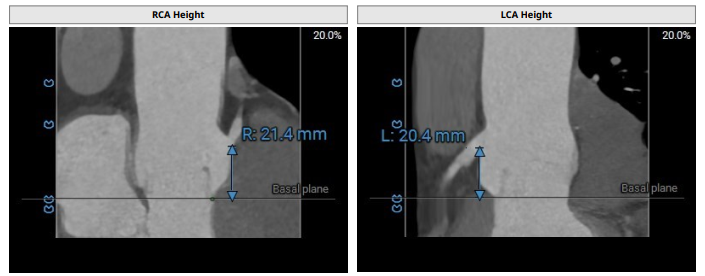

术前影像评估提示,患者主动脉为三叶瓣,无明显钙化,瓣窦分布不均。主动脉瓣环直径28.8mm,左心室流出道直径28.0mm,冠脉开口高度充足(左冠20.4mm,右冠21.4mm),左室与主动脉夹角126°。

CTA评估(上下滑动查看更多照片)